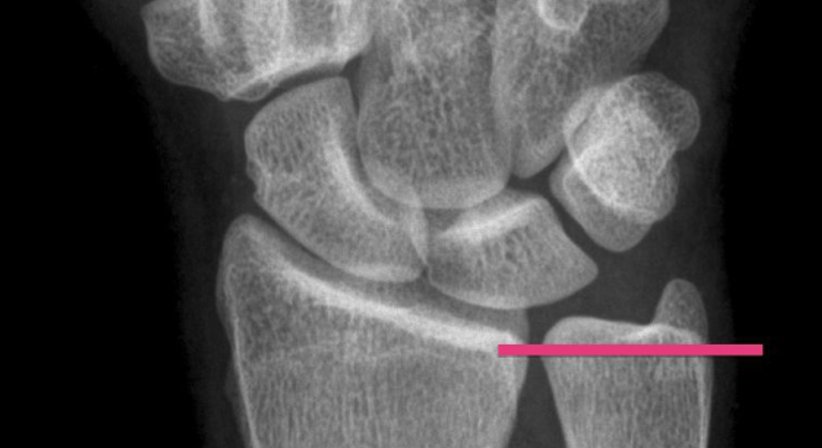

Wenn die klinische Untersuchung den Verdacht auf ein Ulna-Impaction Syndrom ergibt, ist eine bildgebende Untersuchung notwendig. Es werden Röntgenbilder vom Handgelenk in zwei Ebenen und eine Belastungsaufnahme direkt in der Ordination durchgeführt. Hierauf kann eine Überlänge der Elle in aller Regel gut erkannt werden. Um eine Schädigung des Handgelenksmeniskus abzuklären, ist zusätzlich eine Magnetresonanztomographie (MRT) notwendig.